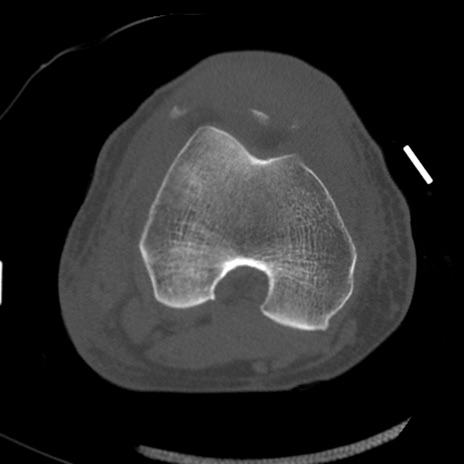

症例28 右膝関節CT(横断像)

右膝関節CT